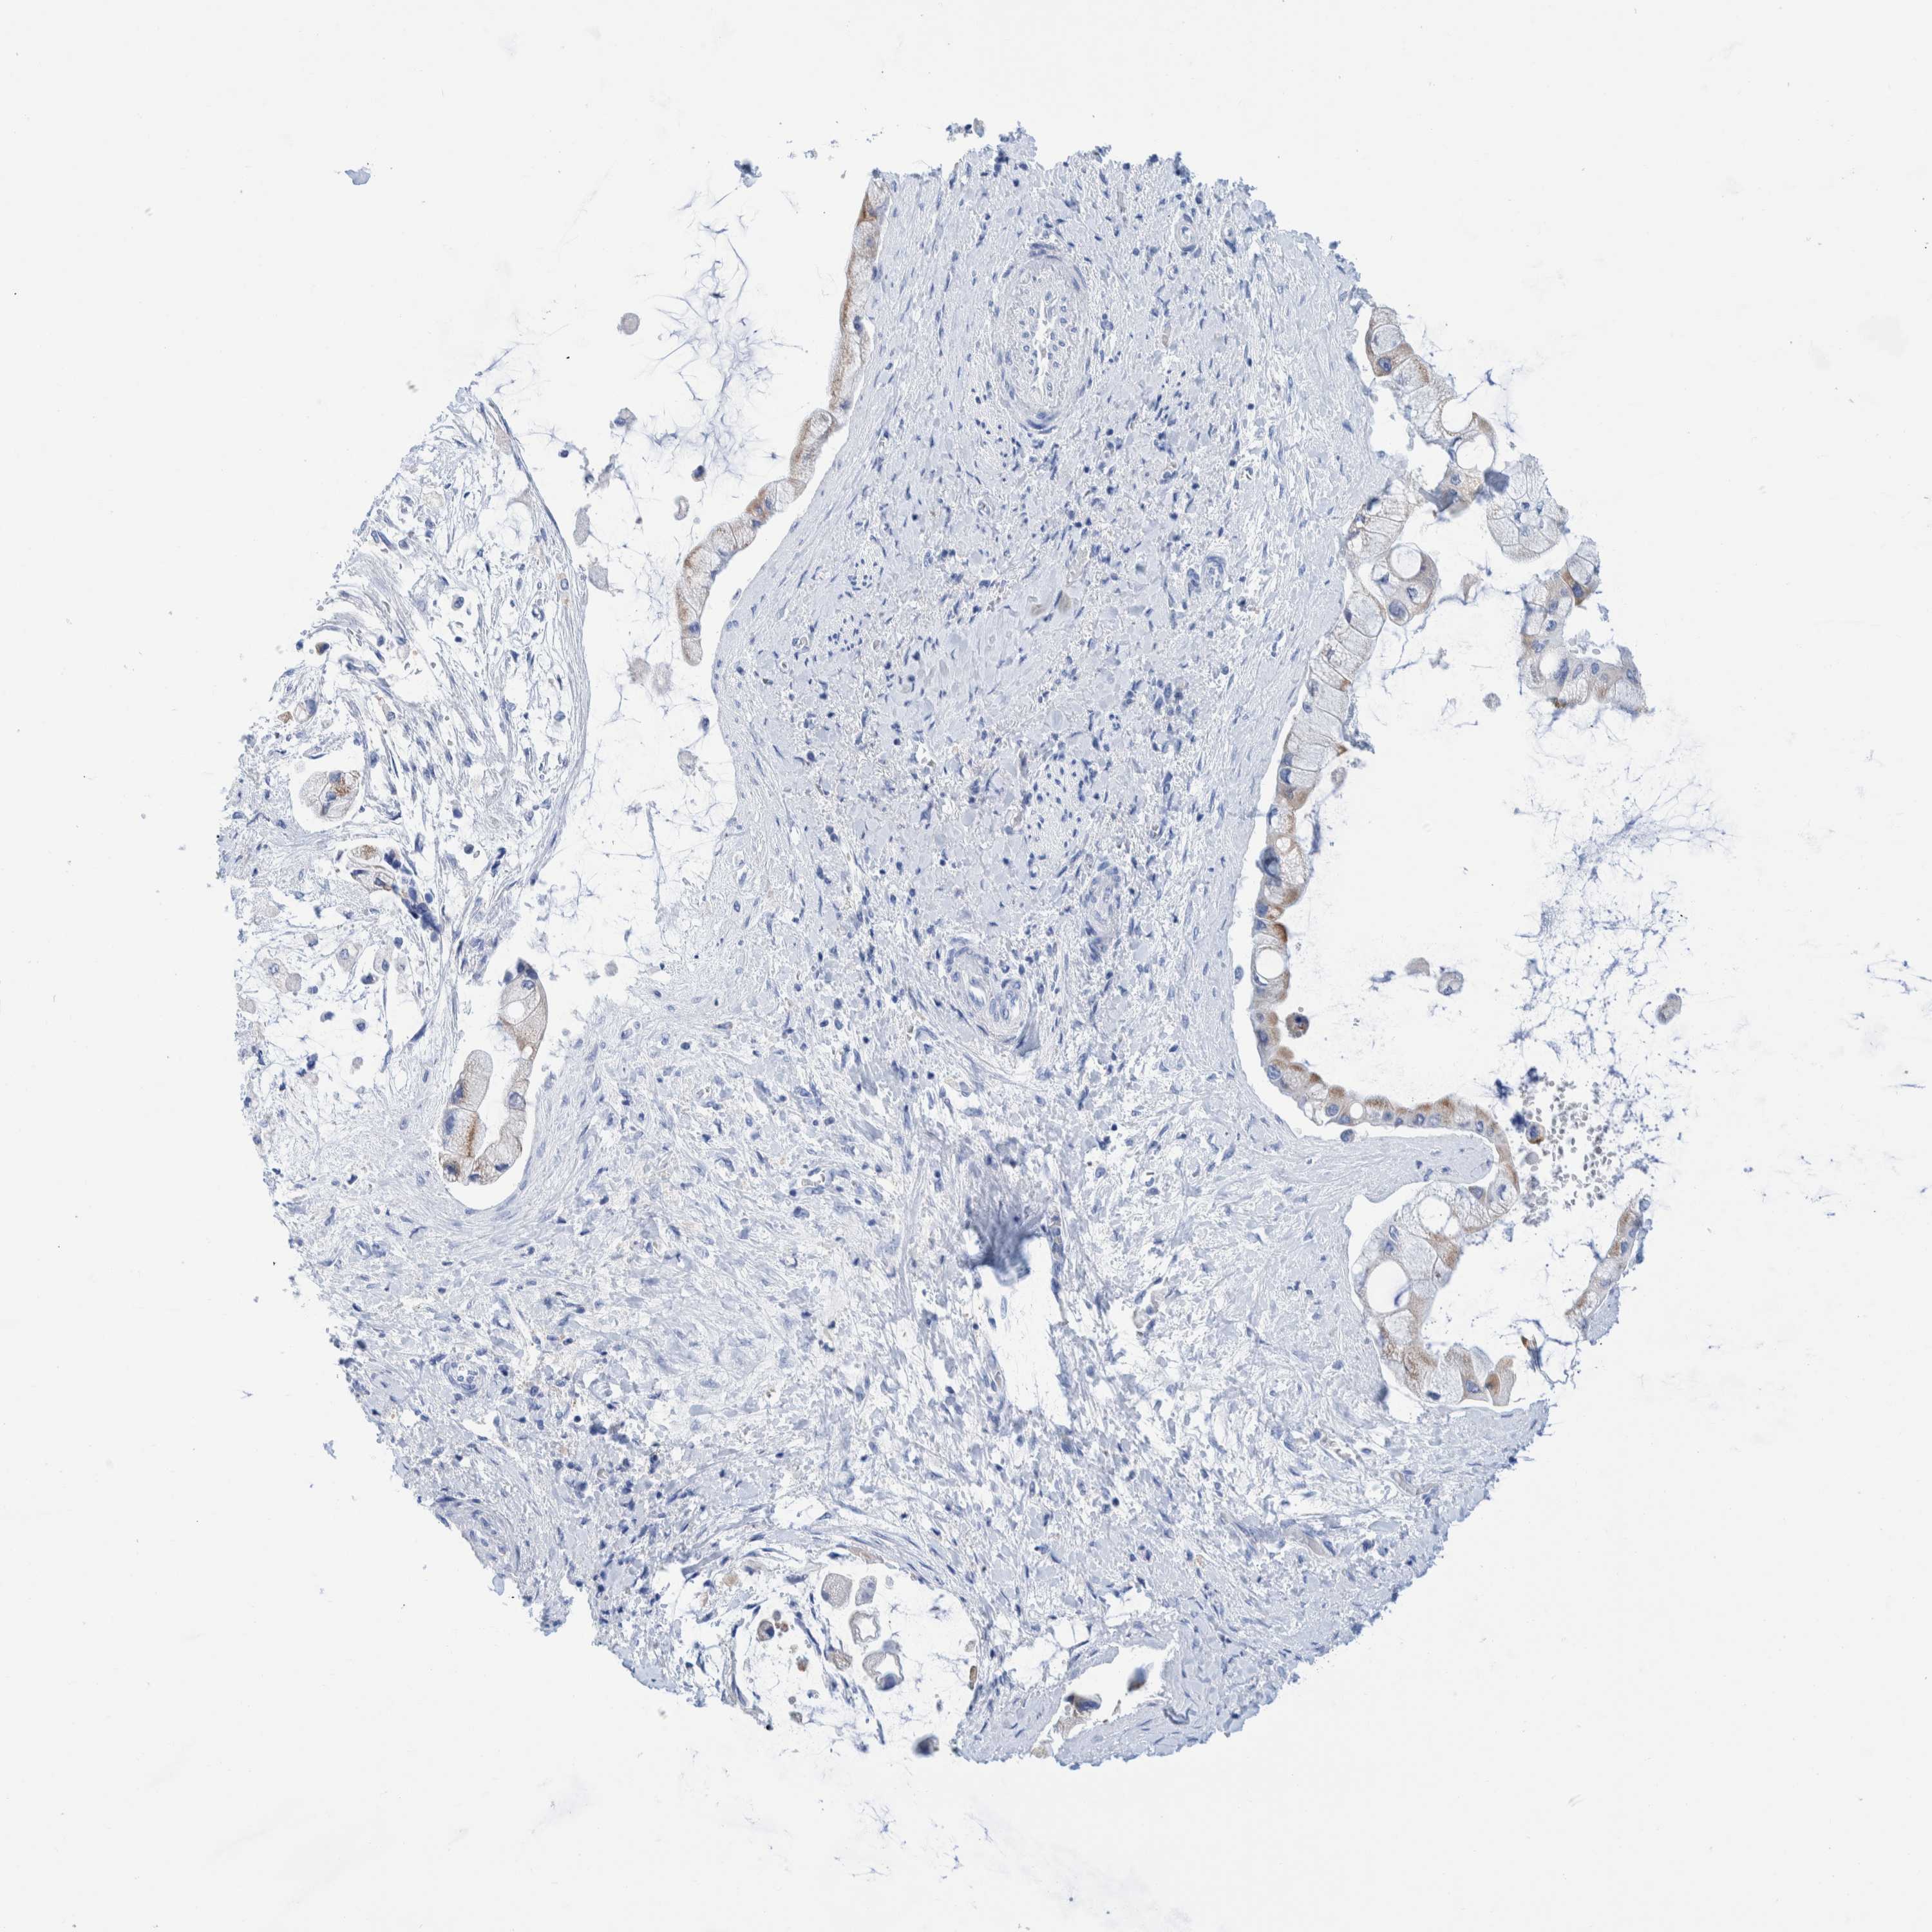

LIVER CANCER - Protein expressioni

A mouse-over function shows sample information and annotation data. Click on an image to view it in a full screen mode. Samples can be filtered based on level of antibody staining by selecting one or several of the following categories: high, medium, low and not detected. The assay and annotation is described here.

Note that samples used for immunohistochemistry by the Human Protein Atlas do not correspond to samples in the TCGA dataset.

Antibody stainingi

Antibody staining in the annotated cell types in the current human tissue is reported as not detected, low, medium, or high, based on conventional immunohistochemistry profiling in selected tissues. This score is based on the combination of the staining intensity and fraction of stained cells.

Each image is clickable and will lead to virtual microscopy that enables deeper exploration of all samples and also displays staining intensity scores, fraction scores and subcellular localization as well as patient and tissue information for each sample.

Antibody HPA000452

Antibody HPA023040

Antibody CAB000134

Carcinoma, Hepatocellular, NOS

Cholangiocarcinoma